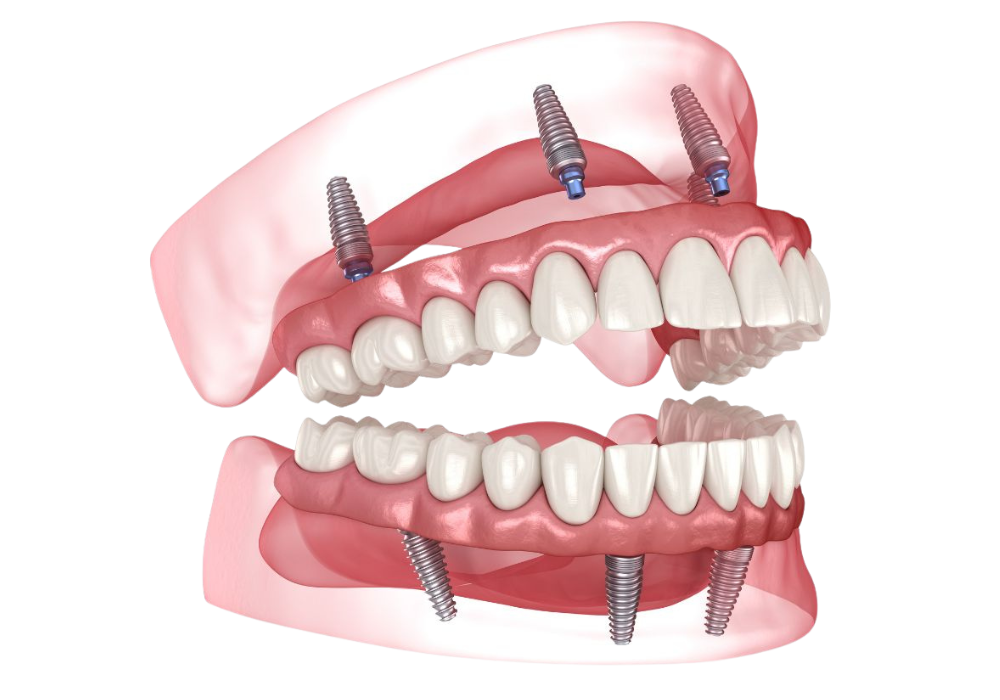

La prothèse fixe sur implants

Une série d’implants est placée dans la mâchoire pour supporter un bridge complet fixé de manière permanente.

Cette solution offre un confort maximal : les dents sont solidement ancrées, ne bougent pas et permettent une mastication naturelle.

La prothèse amovible stabilisée sur implants

Les implants servent alors de points d’ancrage, assurant une excellente stabilité tout en facilitant le nettoyage et l’entretien. Cette technique est principalement réservée pour la mâchoire inférieure

Les implants se soudent naturellement à l’os de la mâchoire (ostéointégration), assurant la stabilité de la future prothèse.Mise en place de la prothèse définitive

Une fois la cicatrisation terminée, la prothèse fixe ou amovible est posée et ajustée avec précision pour un résultat à la fois fonctionnel et esthétique.